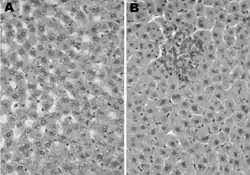

LEC rats - acute hepatitis and hepatoma

An LEC rat, an inbred mutant rat, which suffered from hereditary hepatitis, was examined for elucidation during the development of the acute phase of hepatitis by quantitative analyses of the liver and laboratory data on serum enzymes. The progression of the acute hepatitis in the LEC rat was observed, showing only a few enlarged hepatocytes and Councilman bodies in its early life. These appeared around 8 weeks of age without any clinic signs of hepatitis. The acute phase of hepatitis started with a major increase of Councilman bodies, large nuclei, and hepatocytes in mitosis in the liver around 3-4 weeks before the onset of fulminant hepatitis. From these observations, three stages of progression of acute hepatitis were proposed in the LEC rat.[12]